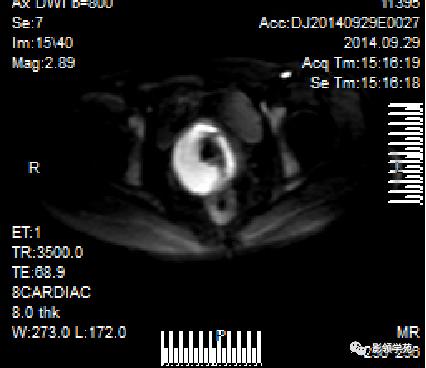

DWI:局限性高信号,癌组织ADC值<癌旁组织<小于正常宫颈组织

宫颈癌术后复发患者,DWI上病灶较T2 fs及T1+C更加明显

DWI显示淋巴结肿大